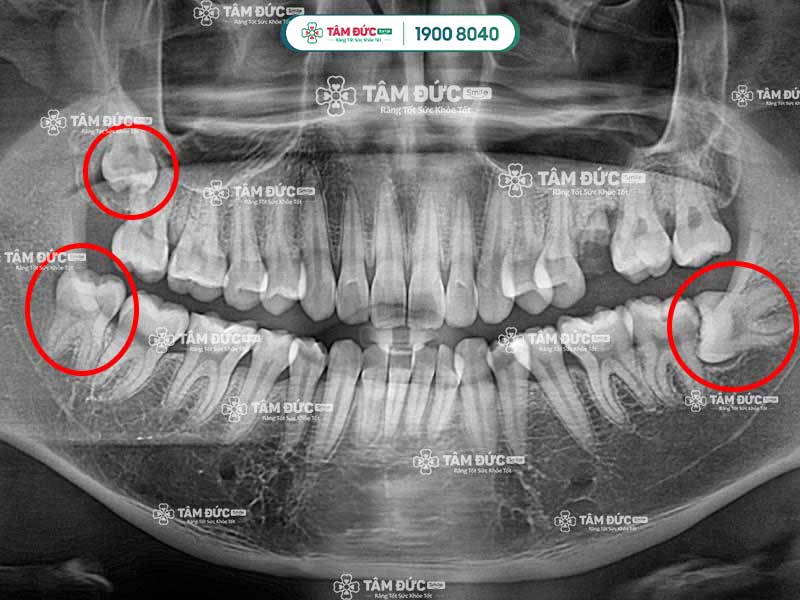

Răng khôn là chiếc răng hàm số 8, thường mọc vào giai đoạn 17–25 tuổi, nằm ở vị trí cuối mỗi cung hàm. Dù là một phần của cấu trúc răng miệng, răng khôn mọc lệch, răng khôn mọc ngầm hay răng khôn gây sưng má lại thường kéo theo nhiều biến chứng như đau nhức, viêm lợi răng khôn, sốt hoặc thậm chí ảnh hưởng răng kế bên. Với công nghệ gây tê hiện đại, nhổ răng khôn không đau bằng sóng siêu âm tại Nha khoa Tâm Đức Smile giúp xử lý triệt để các vấn đề tác hại răng khôn, mang lại sự nhẹ nhõm và phục hồi nhanh chóng cho khách hàng.

4.1. Các trường hợp mọc răng số 8 gây đau

Đa số các trường hợp mọc răng số 8 đều sẽ gây đau, rất hiếm khi răng khôn mọc bình thường. Khi răng khôn mọc, Quý khách cảm thấy đau vùng nướu trong cùng, rất khó chịu. Ngoài ra, răng khôn mọc còn có thể xuất hiện thêm các triệu chứng như: Chảy máu, nhức đầu, hôi miệng,…

Răng số 8 sẽ gây đau trong các trường hợp mọc ngầm, mọc lệch, mọc đâm vào răng số 7,… Mặt khác, sự phát triển của răng khôn cũng làm cho bề mặt nướu bị phá vỡ, từ đó gây đau nhức dai dẳng. Sở dĩ mọc răng khôn gây đau vì lúc này xương hàm đã phát triển hoàn thiện, không đủ chỗ cho răng khôn mọc lên.